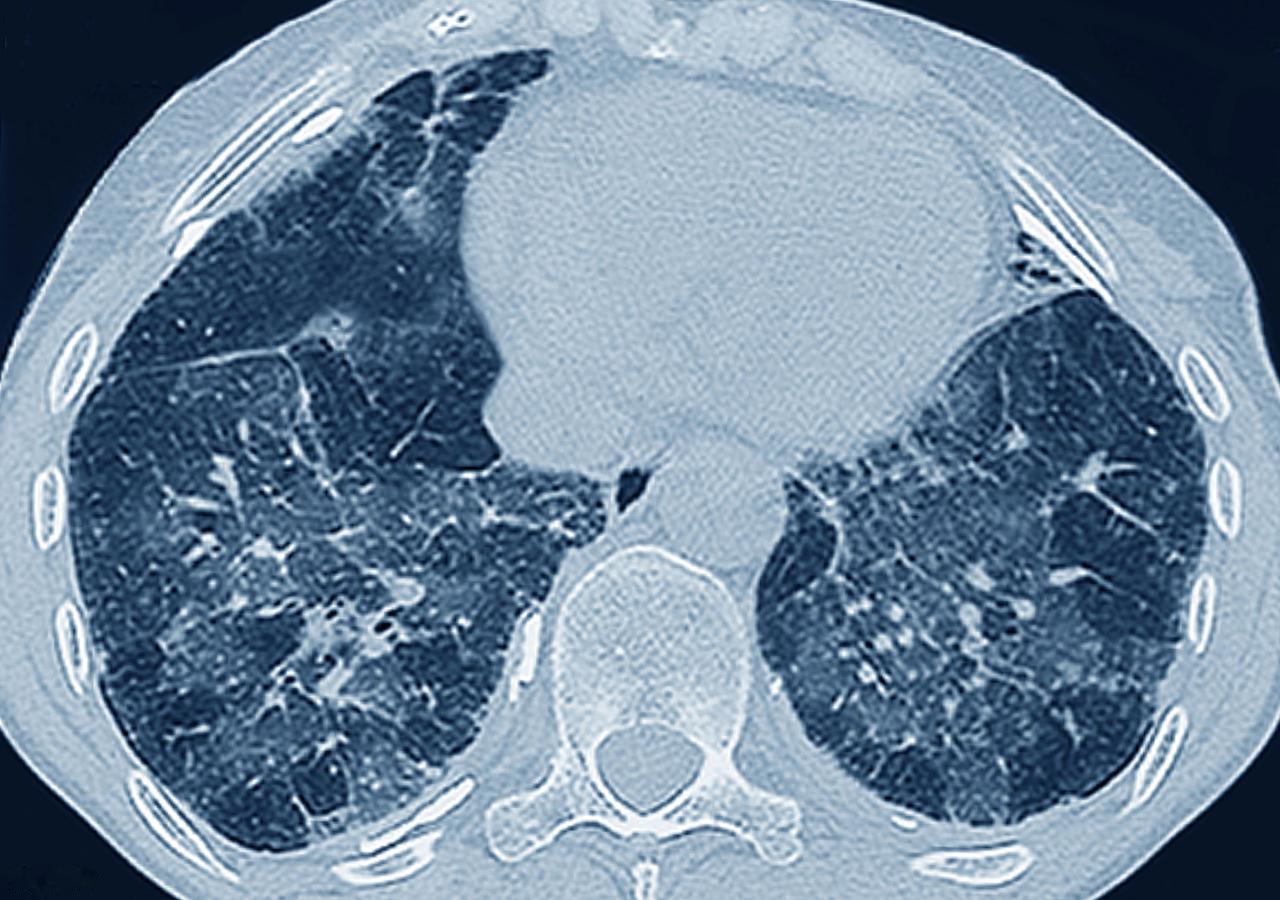

比肺癌更可怕的5个肺部疾病,有的时候来不及抢救,甚至导致猝死终末期的慢阻肺,慢

疾病 慢阻肺 肺癌 呼吸衰竭